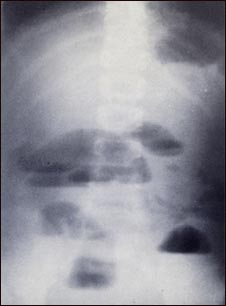

Radiografía de obstrucción del intestino delgado

Las radiografías de abdomen son muy importantes para diagnosticar la presencia de obstrucciones en el intestino delgado. De existir, la obstrucción intestinal hace que se acumule fluido y gas en el intestino, produciéndose un patrón característico llamado "nivel de aire y fluido". El aire se sitúa por encima del fluido y queda una superficie plana en el sitio donde el aire y el fluido se topan.